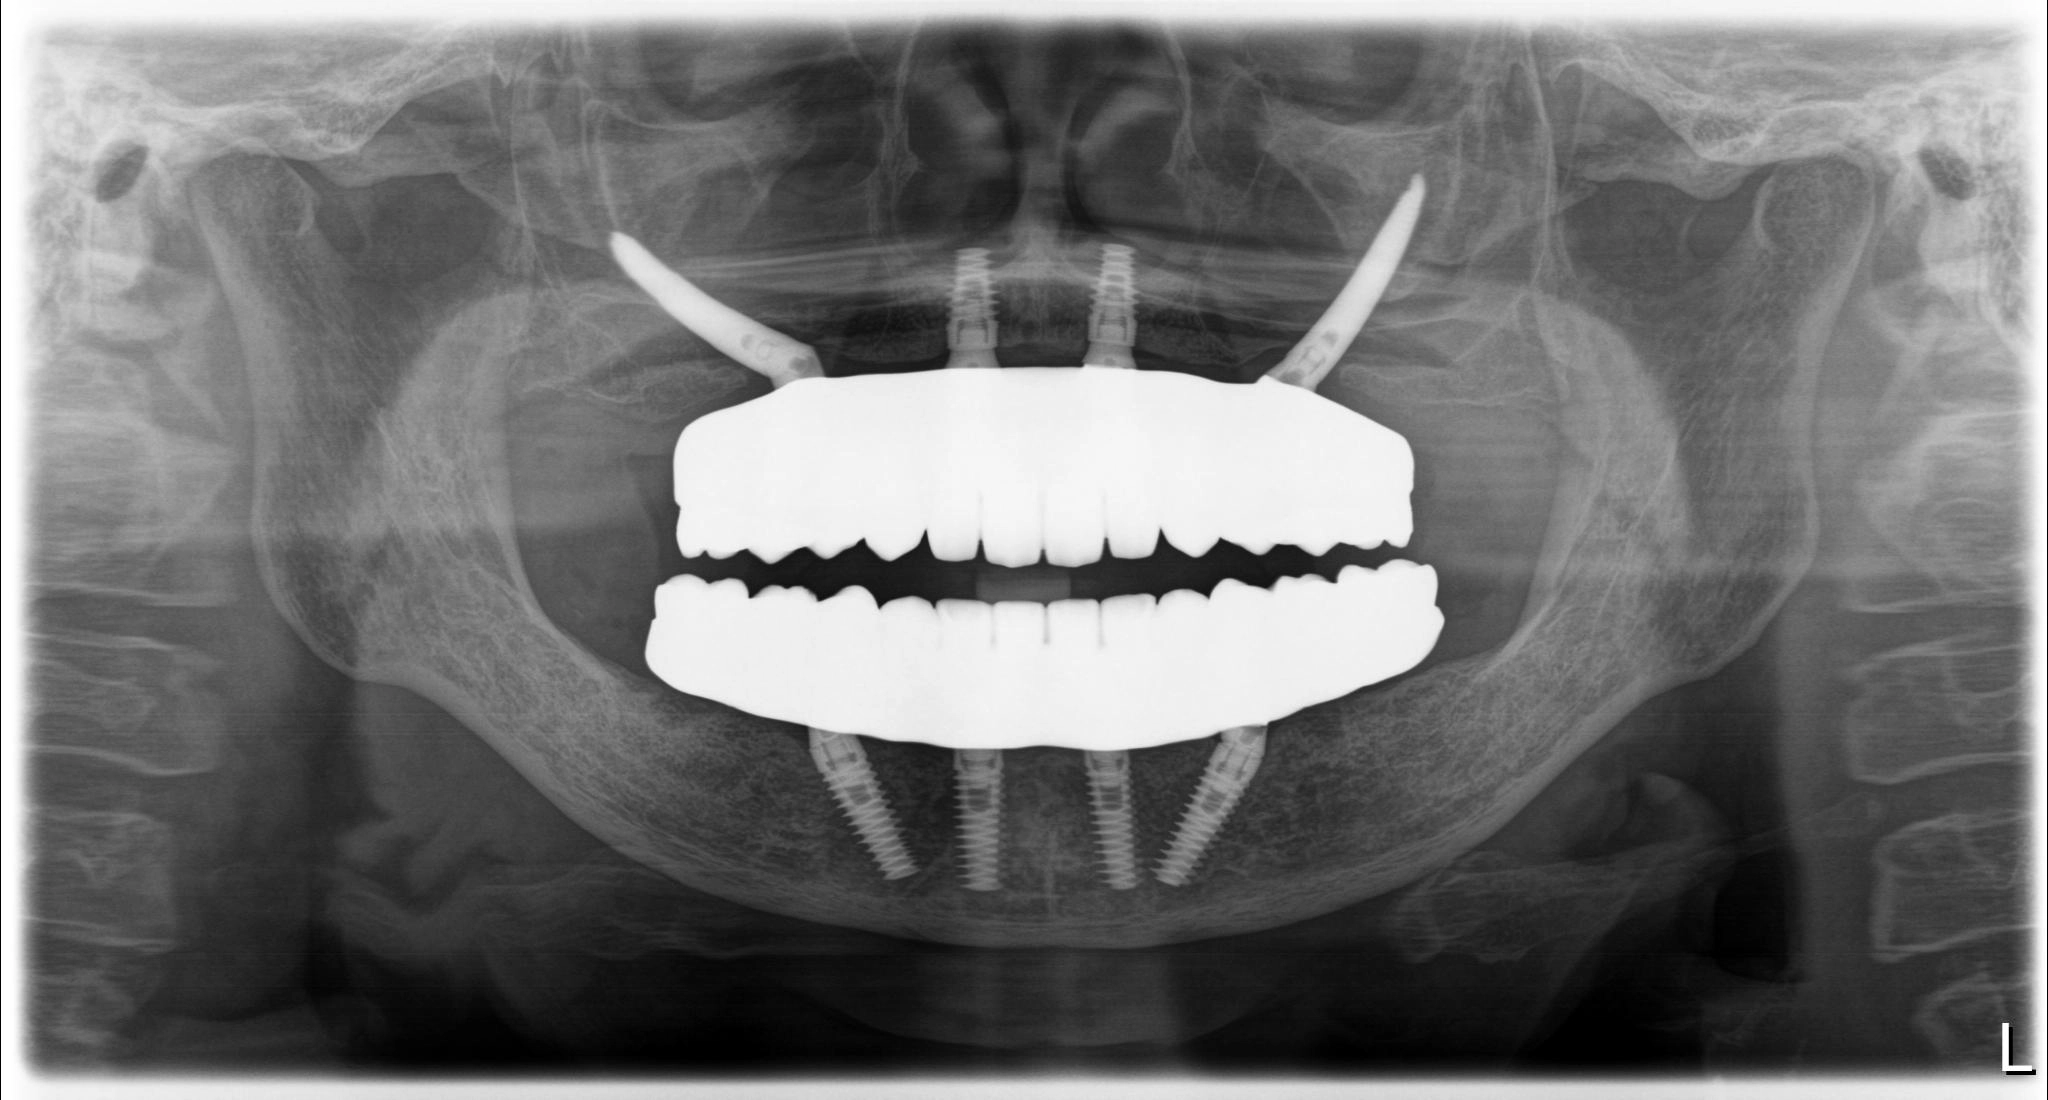

術前

術後

内容 :上下顎オールオン4ザイゴマ2

費用 :4,963,200円

※モニター価格

期間 :半年

リスク:出血・腫れ・痺れ・痛み